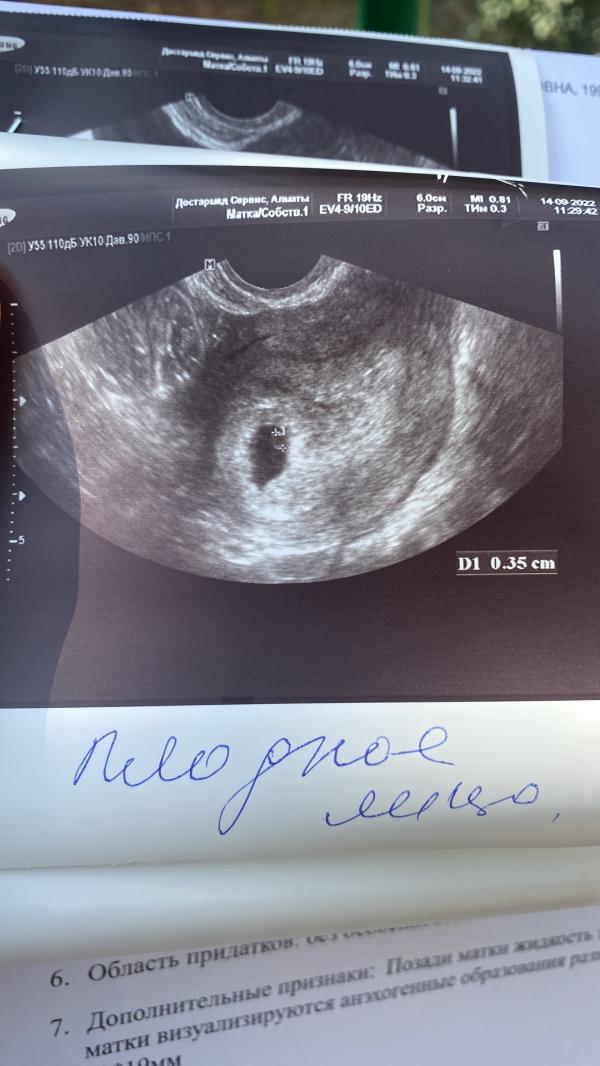

Так как мы планировали уже давно, до беременности я все болячки пролечила, была жидкость за маткой, мазок плохой, но на последних узи и результатах мазка всё хорошо. И вот мы, наконец, решились, забеременела, а тут такое. 11.09 пошла кровь (6 неделя), не так много, но для имплантационного кровотечения вроде поздновато, поехали в 12 гор.больницу, беременность подтвердили, на узи все норм сказали, но эмбриона ещё нет. Гинеко...